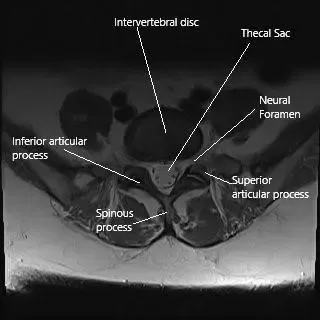

Axial section of the lumbar spine at L5 level.